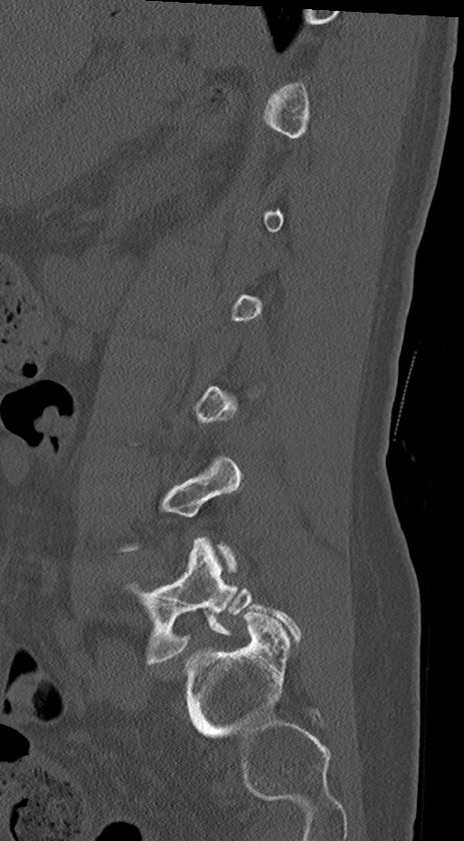

腰椎CT

冠状断像